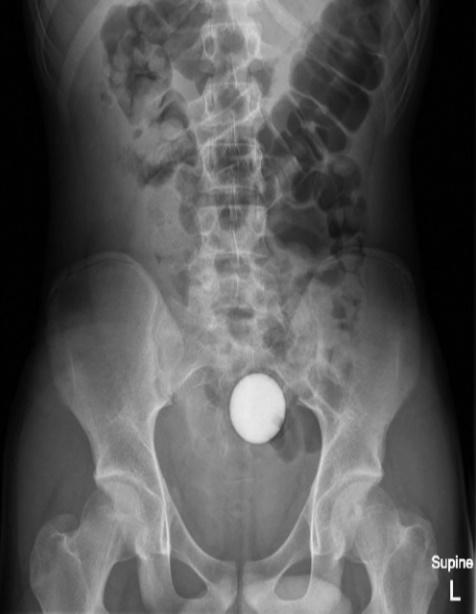

報告指出,這名少年將高爾夫球塞進自己的肛門,惟愈塞愈深,最後竟塞進腸道,雖然少年指無感到劇烈疼痛,但眼見自己已無法處理,只好向母親求助前往就醫。少年指出,雖然球球跑進體內,但他並沒有感受到劇烈疼痛感。X光顯示,一顆球體就在腹腔內。醫生決定先後使用醫療網、導管、吸引器等6種方法,希望將高爾夫球取出但失敗,折騰了2小時後,醫生亦要暫停休息。

醫生建議治療方法首選是瀉藥

24小時後,醫生再為少年照X光,但高爾夫球依然卡在腹腔,但少年的家屬不願意再讓少年接受入侵性治療,因此醫生轉開大量瀉藥,令少年最終「屙」出這顆高爾夫球,少年的腸道及胃道亦沒有受損,身體狀況一切正常,隨後就讓少年出院,但也警告他「不要再將東西塞入肛門直腸」。醫師除了在期刊上公開這起病例,亦在報告中強調,如果有異物進入病患體內,若病患的腸胃道正常的情況下,建議治療方法首選是瀉藥,以用最自然的方法將異物排出。